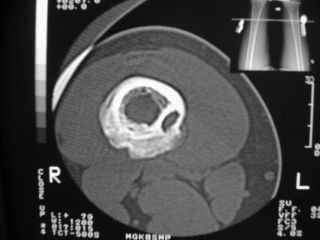

Анамнез практически никакой: в следствие травмы (растяжение связок коленного сустава) от 07.11.2004 выполнены Rg-граммы в травмпункте и обнаружено опухолевидное образование. Первичные Rg-граммы я не публикую, так как они заметно худшего качества, да и динамики за прошедшие три недели не отражают. Болевой синдром купирован в течение трёх дней. В настоящий момент мальчика ничего не беспокоит. Ходьба не нарушена, опухоль пальпируется с трудом по задней поверхности в н\3 правого бедра, пальпация безболезненна, объем движений в суставах правой нижней конечности полный и симметричный. Кожа над опухолью не изменена.В нашей клинике проведено дополнительное обследование: общие анализы крови и мочи, биохимия крови без особенностей. Выполнены Rg-граммы на цифровом Siemens обычные и продольные томограммы срезами 3-5 мм, а также компьютерная томография поперечными срезами по 5 мм. Прошу обратить внимание, что на приведённых томограммах видны две полости 10х15 мм и 15х60 мм. Также имеются два опухолевидных образований наслаивающихся друг на друга: уплощённое и вытянутое 10х100 мм и элипсовидной формы 15х30 мм. Это хорошо заметно на фото a_1.jpg c_1.jpg и d_1.jpg. Плотность внутри полостей 125% от плотности костномозгового канала, плотность наружного опухолевидного образования 55% от плотности кортикального слоя. Также отмечается линия перелома по центру наружного опухолевидного образования.Исходя из полученных данных мнения в плане диагноза несколько разделились от 1)сочетания кортикальной фиброзной дисплазии и латентно протекавшего маршевого перелома н\3 правого бедра до 2)остеосаркомы. В отношении первого варианта не сходится отсутствие клиники при переломе такой крупной кости как бедро, второй вариант вообще оставлю без комментария, ибо некомпетентен. Хотелось бы услышать мнения коллег, с удовольствием ознакомлюсь с любыми предположениями и замечаниями.С уважением, Александр Е. КлоковОтделение детской ортопедии и травматологииБСМП г. Мурманска.